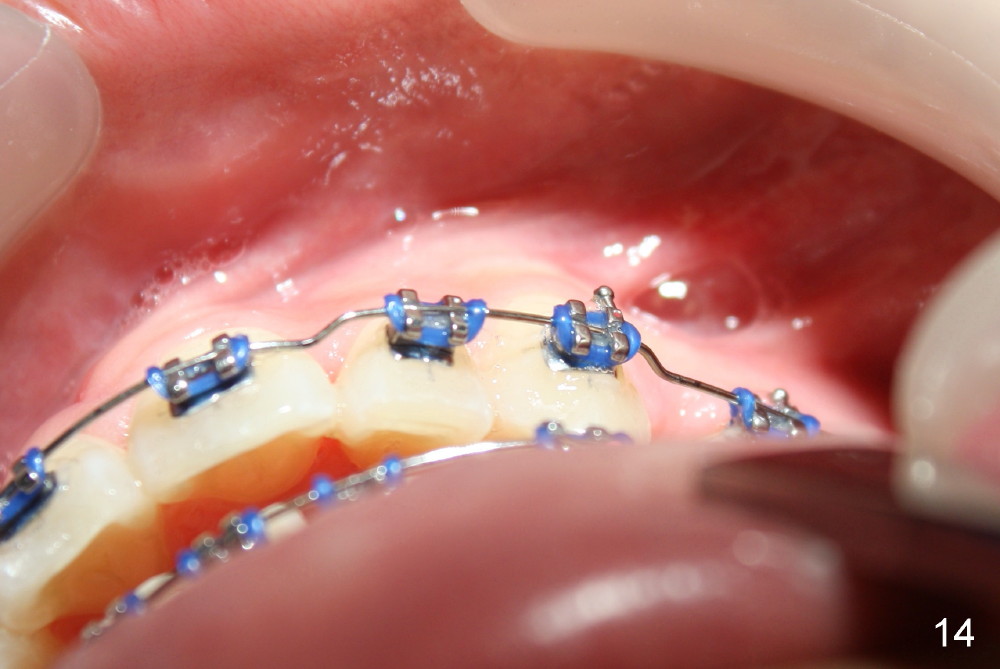

The kid returns 1 month 10 days after last visit. Wires change to 16x22 ss with figure-8 wires placed between UR3 and UL4 and between LL3 and LR 4 (Fig.41-45). A separator is placed between LL6 and 7.